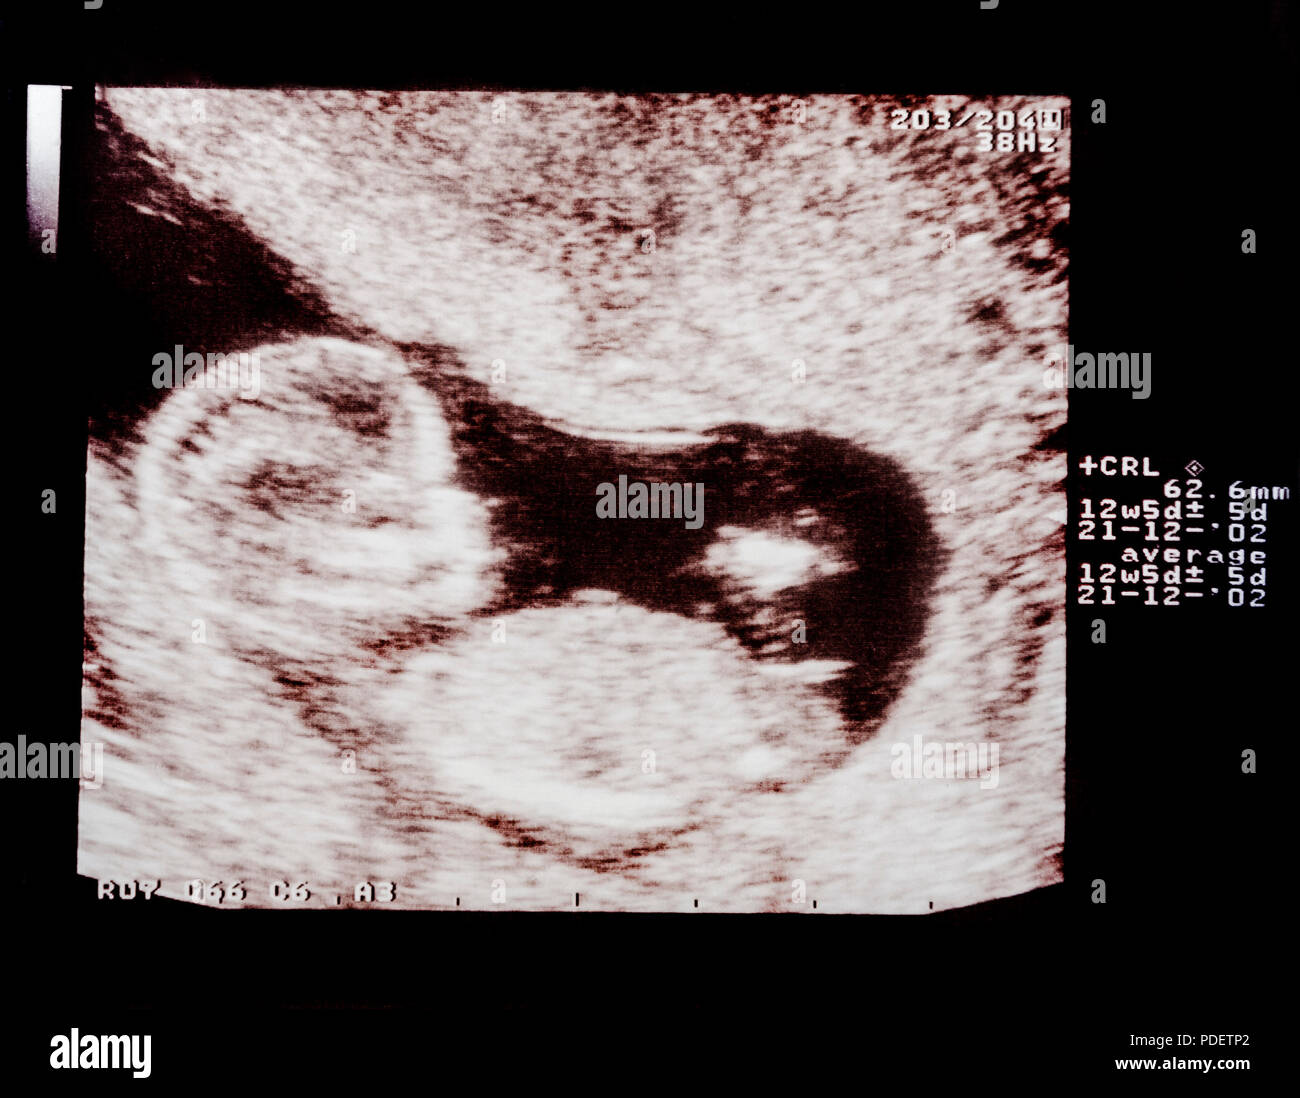

Photos of the Child in the 12 Week of Pregnancy. Ultrasound Procedure …